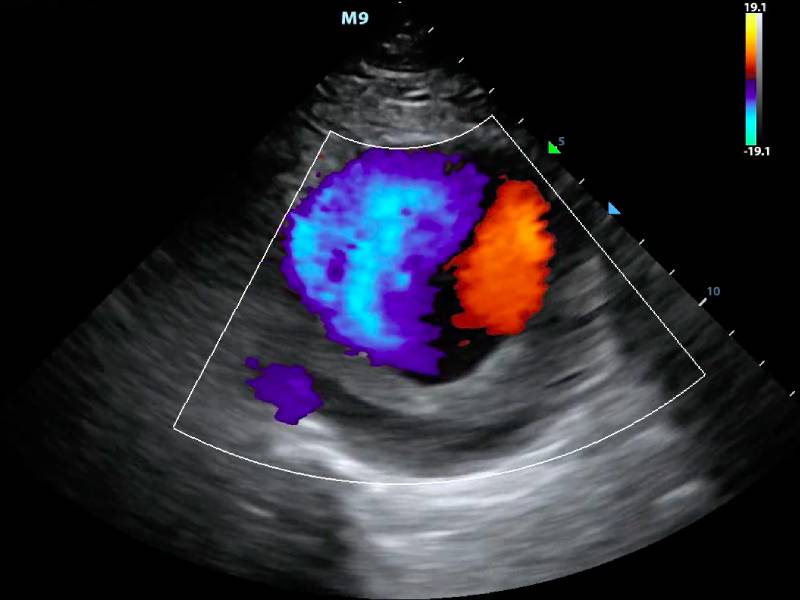

Sanya Karond Imaging Center offers advanced Colour Doppler services, a non-invasive method that uses ultrasound waves to visualize blood flow in arteries and veins. This technology is instrumental in diagnosing conditions such as deep vein thrombosis (DVT), peripheral artery disease (PAD), and other vascular disorders.

Dr. Anil Kumar, a seasoned radiologist at the center, conducted the Colour Doppler test. The results were swiftly processed, and within a short time, the mystery of Meera’s mother’s leg pain was unveiled. It was diagnosed as a case of peripheral artery disease, a condition that could be managed effectively with the right treatment plan.